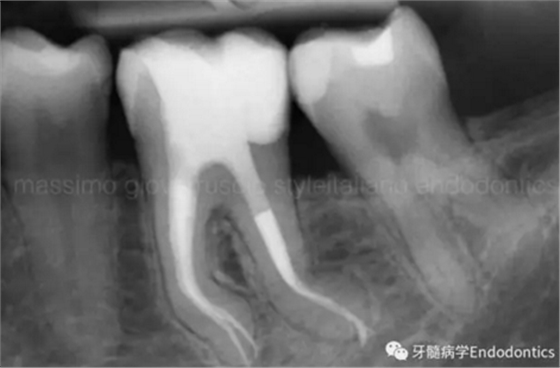

圖11.術(shù)后X片顯示完成了根管的三維充填并很好地保留了復(fù)雜的解剖形態(tài)結(jié)構(gòu)。

圖12.對于較為困難的病例,探查根管時(shí)可能需要很多嘗試。一旦銼的尖部繞過了阻礙,會深入根管。

圖13.在探查的過程中,銼的硅膠止片的方向可以提示醫(yī)師銼尖越過障礙時(shí)彎曲的方向,即描述了通路的方向。扭動銼使其進(jìn)入的更深,使用根尖定位儀檢查,直到到達(dá)全長。

圖14.一旦通過了障礙,應(yīng)避免將銼退出至障礙水平,因?yàn)殇S會不可避免的被拉直,之后除非將銼完全退出,重新預(yù)彎,重新插入,否則無法通過障礙。在S形彎曲根管內(nèi),存在兩處障礙,當(dāng)銼繞過根管內(nèi)第一處障礙后會在第二個彎處再次遇到根尖方向的阻力。在這樣的病例中,將銼稍微回退少許,旋轉(zhuǎn)180度,輕輕扭動,觀察銼是否能到達(dá)全長。

圖15.通過預(yù)彎的銼和止動片的指示,你應(yīng)該能夠在腦海中描繪出障礙附近的根管路徑,隨后輕松的通過障礙,完成工作!